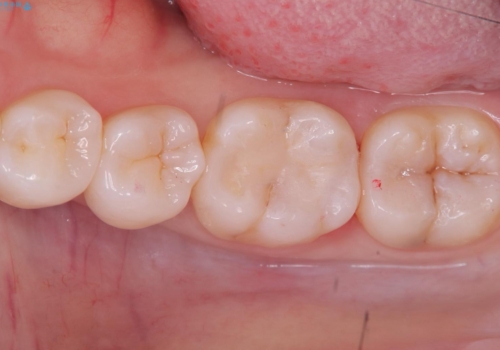

- 主訴:左下の奥歯がなんだか他の歯に比べて青白い気がする。虫歯じゃないか見てほしい。

左下6番目の歯の咬合面で虫歯が進行しており、プラスチックを用いた治療とセラミックを用いた治療を提案し、適合や材料安定性の良いセラミックインレーでのやり替えとなりました。

咬合面のカリエスの場合、CR修復で済ませることが多いですが、CRは経年的に劣化し二次う蝕を引き起こすリスクがあるため適合や経年劣化しにくいセラミックでの治療となりました。